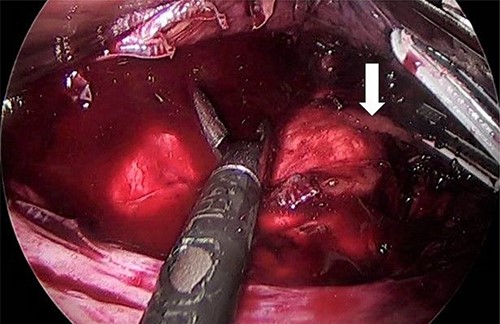

For LLA, ports were inserted similar to our preferences for LSG, which are 5 mm at left upper quadrant, 12 mm at superior and to the right of umbilicus, 5 mm port at right upper quadrant and a Nathanson liver retractor at epigastric area. In Patient 3 with left adrenal mass, we proceeded with LSG first since the patient is not a high risk and that LSG will ease the LLA from exposure standpoint. The greater omentum was divided till the gastroesophageal junction, followed by applying 60 mm black Ethicon Tristapler at the antrum followed by purple staplers along a 36Fr bougie. It is our preference to apply clips long the sleeve but not a full deployment to control bleeding. Using the supragastric approach described before, the left adrenal gland was reached easily using the left diaphragmatic crus as a landmark and tracing the left phrenic vein to reach the left adrenal vein [7]. Using energy device, the left adrenal vein was controlled and attachments were released liberating the left adrenal gland and placed in the endobag. After assuring hemostasis, we completed the procedure by plicating the stomach at the upper half of the sleeve and omentopexy of the whole sleeve till the end of the divided omentum (Fig. 4).

As for the LRA, ports are inserted in similar fashion as the LLA but with more to the right side. An additional port at the right midclavicular line is an optional (Fig. 5). In Patient 1, we started with the LLA to control the blood pressure caused by the adrenal gland and to prevent unnecessary bleeding from occurring. Conversely, we started with LSG in Patient 2 because the priority was controlling his comorbidities by weight reduction. The right hepatic lobe was retracted to expose the subhepatic area. The right hepatic ligaments were released, exposing the inferior vena cava. Dissection lateral to the IVC was continued exposing the right adrenal (Fig. 6). Complete dissection of the adrenal gland was completed and the pedicle was controlled using energy device (Fig. 7). There was constant communication with the anesthesia team during the surgery. After complete dissection of the adrenal gland, it was placed in the endobag and the LSG was conducted similar to the above-mentioned steps (Fig. 8).